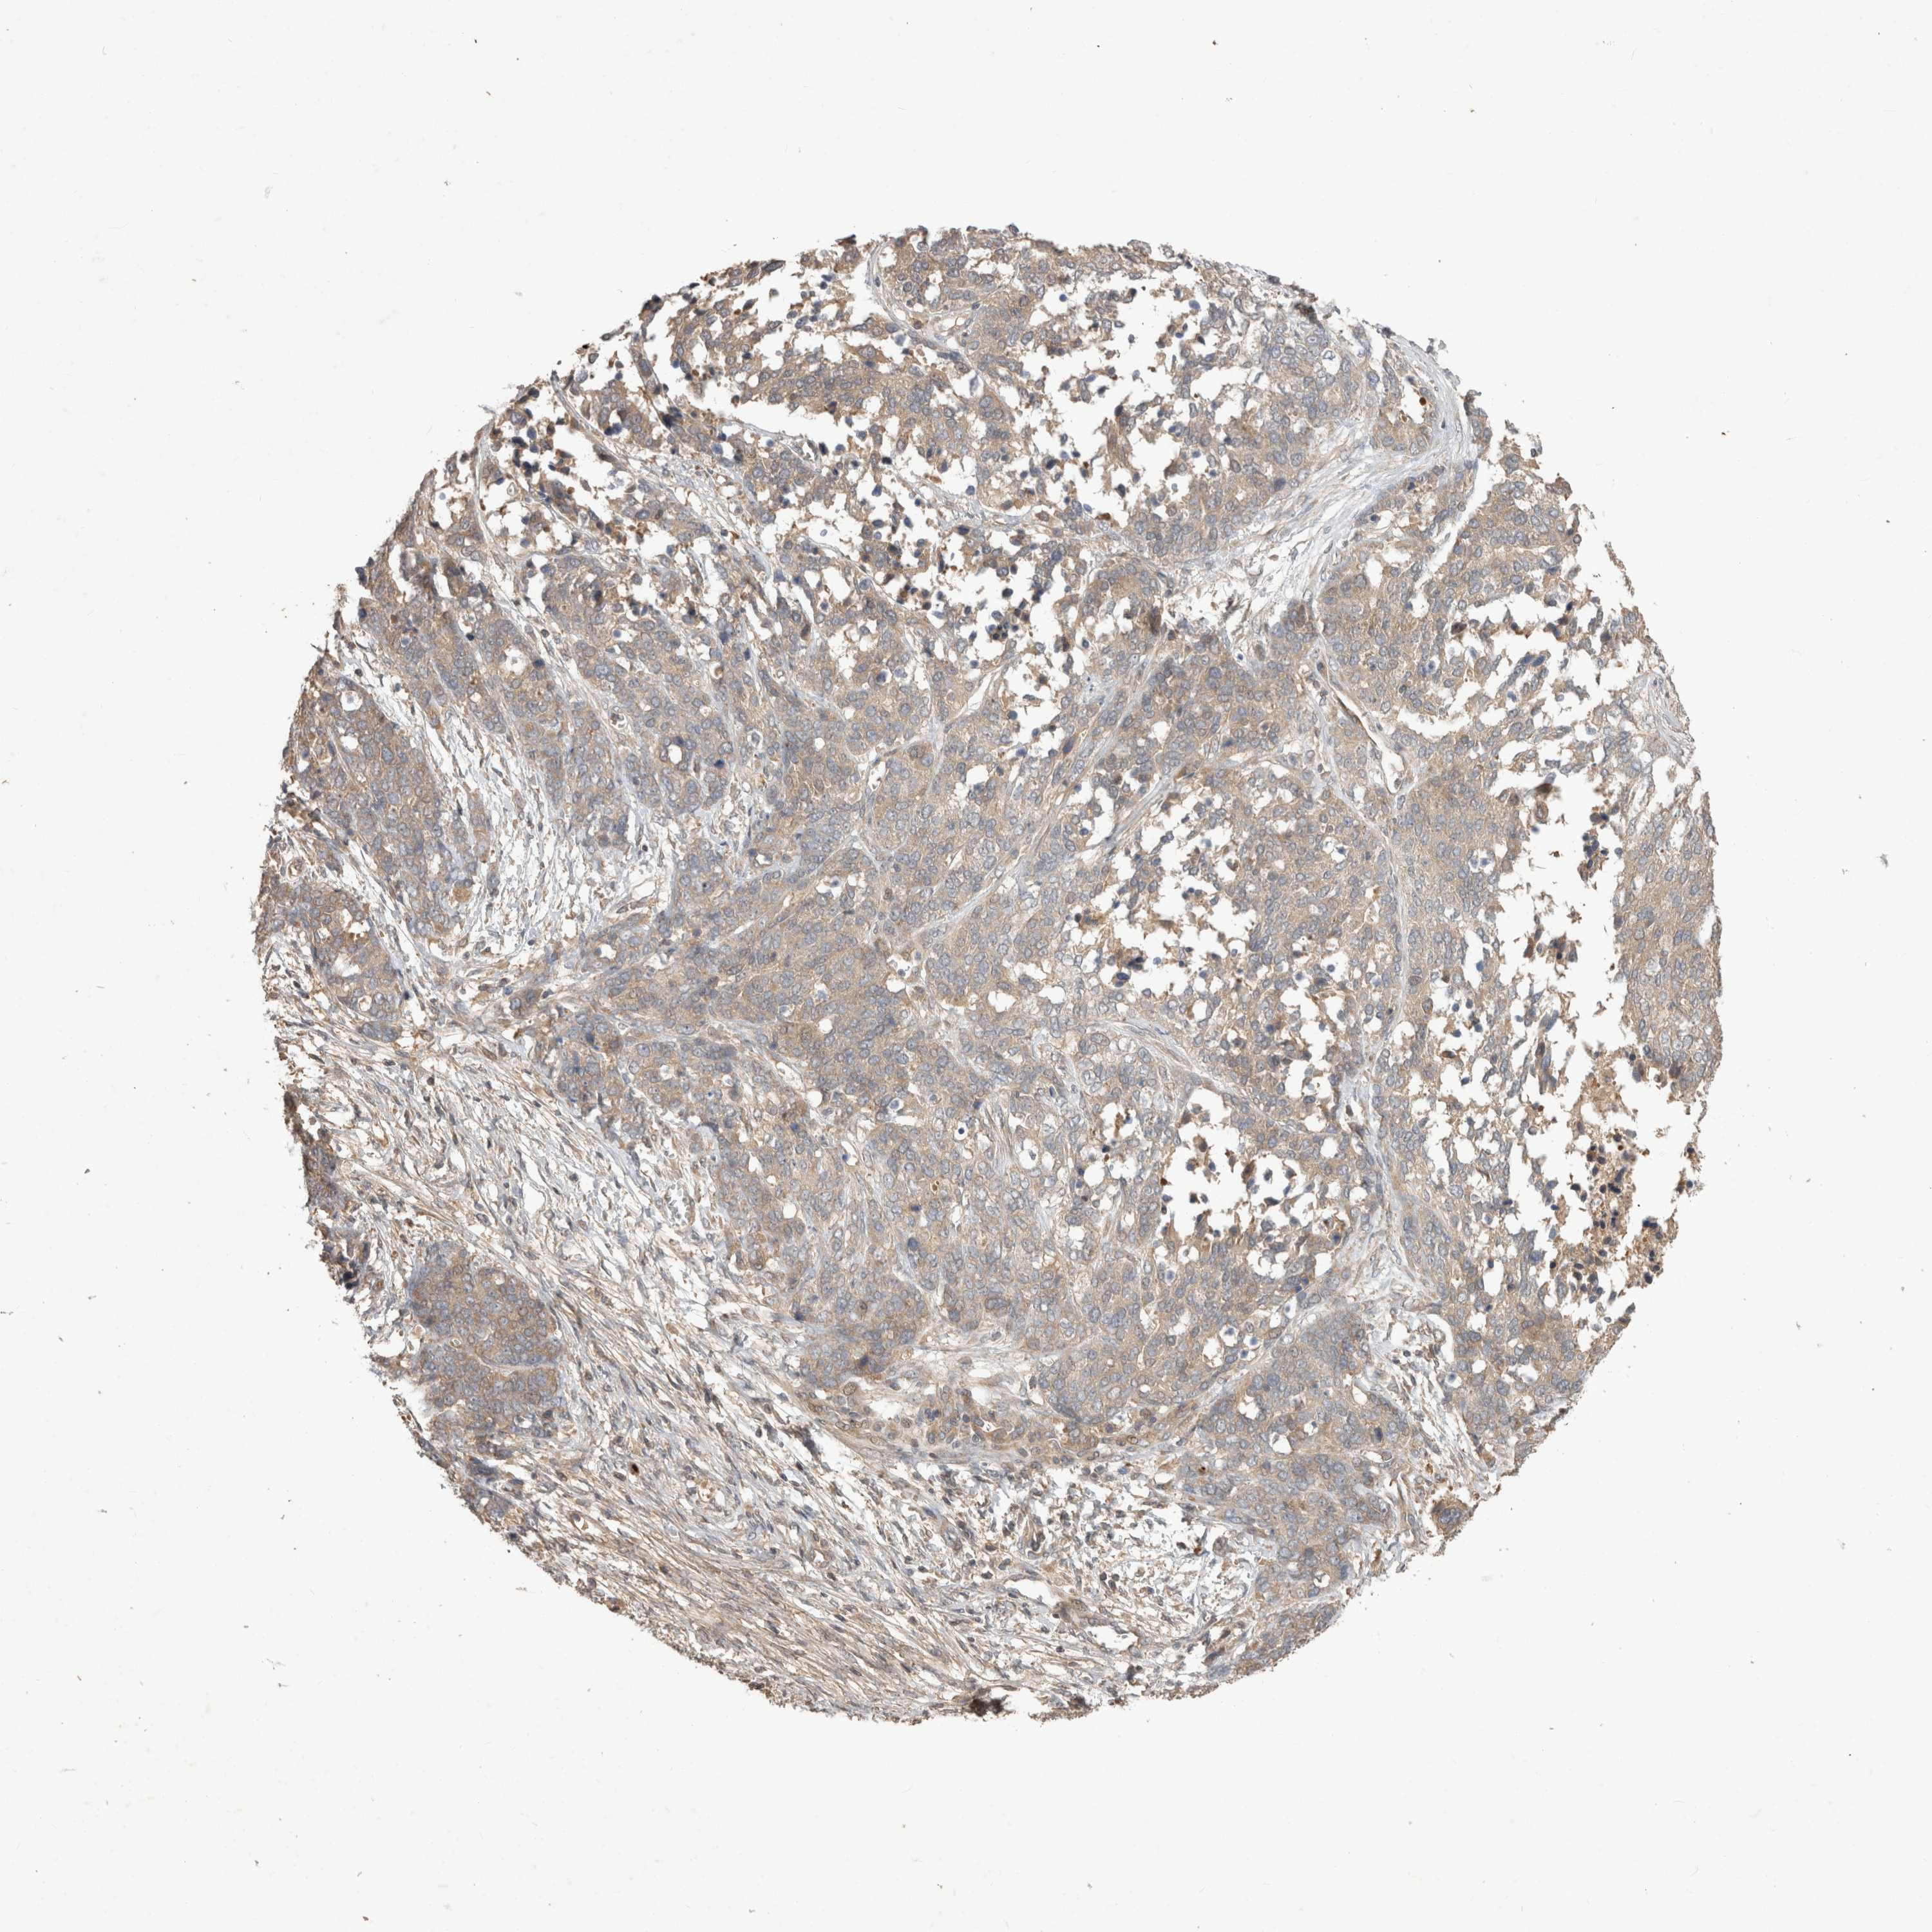

OVARIAN CANCER - Protein expressioni

A mouse-over function shows sample information and annotation data. Click on an image to view it in a full screen mode. Samples can be filtered based on level of antibody staining by selecting one or several of the following categories: high, medium, low and not detected. The assay and annotation is described here.

Note that samples used for immunohistochemistry by the Human Protein Atlas do not correspond to samples in the TCGA dataset.

Antibody stainingi

Antibody staining in the annotated cell types in the current human tissue is reported as not detected, low, medium, or high, based on conventional immunohistochemistry profiling in selected tissues. This score is based on the combination of the staining intensity and fraction of stained cells.

Each image is clickable and will lead to virtual microscopy that enables deeper exploration of all samples and also displays staining intensity scores, fraction scores and subcellular localization as well as patient and tissue information for each sample.

Antibody HPA024313

Antibody HPA027983

Antibody HPA028628

Staining

High

Medium

Low

Not detected

Intensity

Strong

Moderate

Weak

Negative

Quantity

>75%

75%-25%

<25%

None

Location

Nuclear

Cytoplasmic/membranous

Cytoplasmic/membranous,nuclear

Cystadenocarcinoma, mucinous, NOS